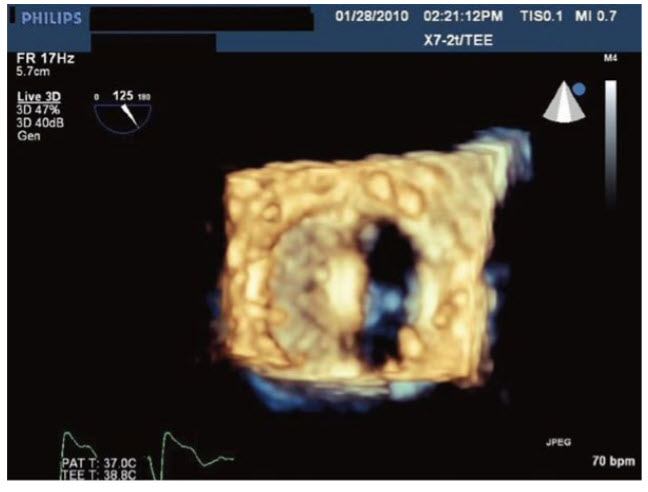

The three-dimensional (3D) transesophageal echocardiographic (TEE) image in Figure below

demonstrates a patient with:

A. Normally functioning bioprosthetic mitral valve replacement (MVR).

B. Normally functioning bileaflet mechanical MVR

C. Mitral valve (MV) endocarditis with a vegetation

D. Abnormal mechanical MVR

E. Abnormal bioprosthetic MVR